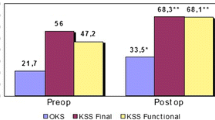

Pre-implantation symptoms were documented with multiple scores: VAS 7.9 ± 1.4 (range, 4.9 to 10), AKPS 34.6 ± 23.3 (range, 7 to 85), and OKS 17.3 ± 10.3 (range, 10 to 41). The average operating time was 81 min ± 22 (range, 60 to 120), the average hospital stay was 4,6 days (range, 3 to 6), while bleeding, calculated as the difference between pre-operative and second post-operative day blood count, was Hb 2.12 ± 0.6 (range, 1.2 to 3.4) without blood transfusions. No patient underwent further surgical gestures to center the patella (e.g. lateral release, tibial tuberosity transposition, MPFL reconstruction).

The average time elapsed from surgery to the latest follow-up was 52 months ± 12.6 (range, 36 to 72). The implant survivorship was high (94.4%) with no surgical or robot-technique related complication recorded. Only one patient experienced, after five years, OA progression in the femoro-tibial compartment, requiring primary total knee arthroplasty revision. Every patient expressed satisfaction or high satisfaction with noticeable enhancement in their quality of life, except for one patient with high pre-operative functional scores (OKS 41), who maintained comparable post-operative results, not reaching his expectation. Radiographic control, performed close to the visit, showed no signs of implant loosening or further OA progression. At the last follow-up, final ROM was excellent in each patient, with mean maximum flexion of 131.1°±10.5° (range, 110° to 145°), while functional scores were VAS 1.10 ± 1.4 (range, 0 to 4), AKPS 90.2 ± 8.6 (range, 73 to 98), and OKS 46.3 ± 1.8 (range, 43 to 48). Pain and functional scales demonstrated significant outcome improvement (P-value < 0.01) between pre-operative and post-operative assessments (Tables 2 and 3).

This is the first series of robotic-assisted PFAs assessed at a minimum follow-up of three years after surgery. We have reported high overall satisfaction and implant survival rates. Almost every patient resolved their primary symptoms raising their quality of life. Administered questionnaires recorded significant enhancement in functional and pain control outcomes at a mean follow-up of four years: VAS improved from 7.9 to 1.10, APKS from 34.6 to 90.2, and OKS from 17.3 to 46.3. We attribute these outcomes to a combination of meticulous patient selection criteria and proper surgical procedure.